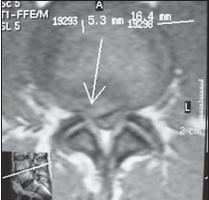

На МРТ № 13 наблюдается медиолатеральная грыжа межпозвонкового диска (заднебоковая) На МРТ № 14 наблюдается фораминальная грыжа межпозвонкового диска с локализацией внутрь межпозвонкового отверстия МРТ № 15 ![]() МРТ № 16

На МРТ № 15 наблюдается двухсторонняя экстрафораминальная грыжа межпозвонкового диска (расположенная за межпозвонковыми отверстиями) На МРТ № 16 наблюдается медиолатеральная протрузия и вентральная грыжа межпозвонкового диска